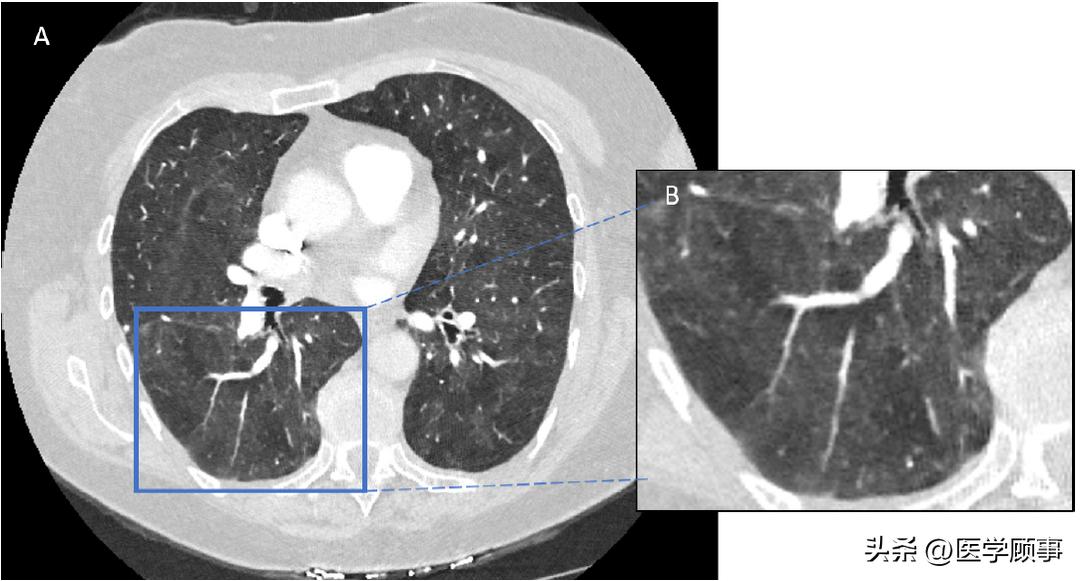

肺部真菌感染的风险和严重程度取决于宿主的免疫状态、真菌种类、暴露于真菌接种物的持续时间和严重程度[15]。肺部真菌感染的临床表现有自限性无临床症状的感染或流感样疾病,在免疫受损的宿主中的播散性威胁生命的疾病。这些病原体往往会在免疫功能低下的宿主中导致发病率和死亡率显著升高,包括患有以下疾病的宿主:血液系统恶性肿瘤、接受免疫抑制药物治疗的宿主、白细胞减少伴中性粒细胞或淋巴细胞功能障碍的宿主,以及实体器官和造血干细胞移植受者[46,48,49]。肺部真菌感染的影像学表现为有或无肺空洞的弥漫性肺结节、实变、团块样阴影(图1)和弥漫性肺部阴影。

图1:肺芽生菌病患者胸部CT扫描显示团块样密度影。图A代表CT扫描的横截面,图B显示所选择CT图像的放大图。